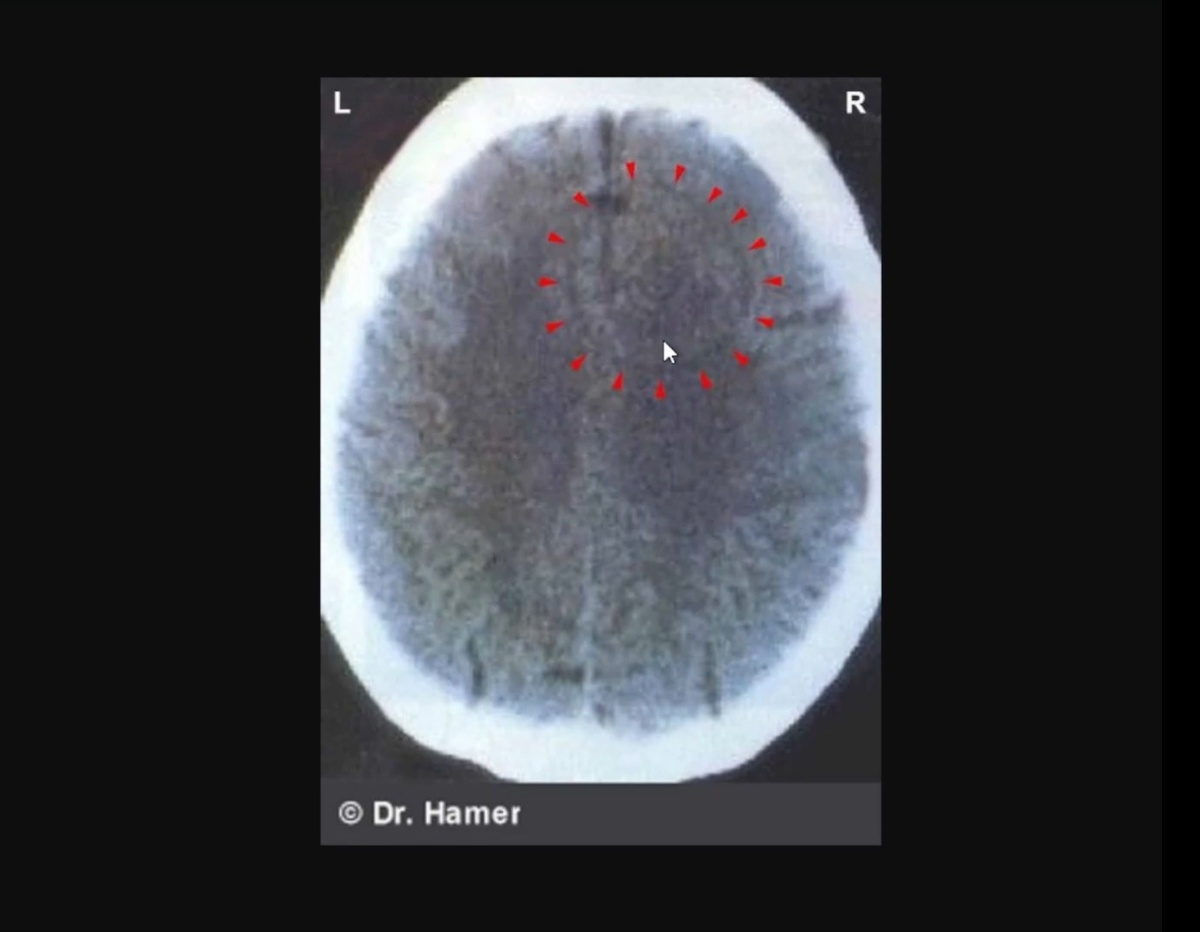

Если смотреть с точки зрения ГНМ, одна из причин образования очагов глиоза – это формирование некой доминанты в мозге в момент активной фазы биологического конфликта, и она напрямую связана с каким-то органом, то есть она находится в зоне мозга, где нейрональные ядра, а может находиться и в белом веществе, если это связано с соединительной тканью мозга. И в момент активности конфликта у нас происходит формирование очага Хамера. Когда конфликт разрешается, формируется глиальный очаг, и чем больше и длительнее продолжался конфликт, тем больше очаг глиоза при разрешении конфликта. И если конфликт сформировал достаточно большую конфликтную массу, то в том месте, которое связано с сутью конфликта, психически связано с органом, который вовлечен в конфликт, формируется очаг глии. В течение нескольких лет очаг глии должен заместиться нормальной тканью. Это описано в биологических законах Хамера, и он опроверг вопрос озлокачествления.

На снимке мы видим очаг, и он-то и указывает на конфликт. И когда конфликт завершается, глиоз начинается не из центра, как гласит теория опухолей. Хамер отнаблюдал, что глиоз начинается от периферии и постепенно заполняет весь очаг.

Первая фаза восстановления – это отек, место становится на снимке темным, затем начинается постконфликтная фаза 2 типа, то есть очаг глиоза, который развивается снаружи внутрь, а внутри здоровые ткани, и это будущая глиома или глиобластома, и это зона разрешения конфликта.